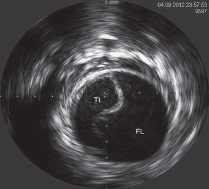

Label the IVUS image below

Adventitia???/?

What are the arrows pointing to in the images below?

dissection

What is happening in the image below